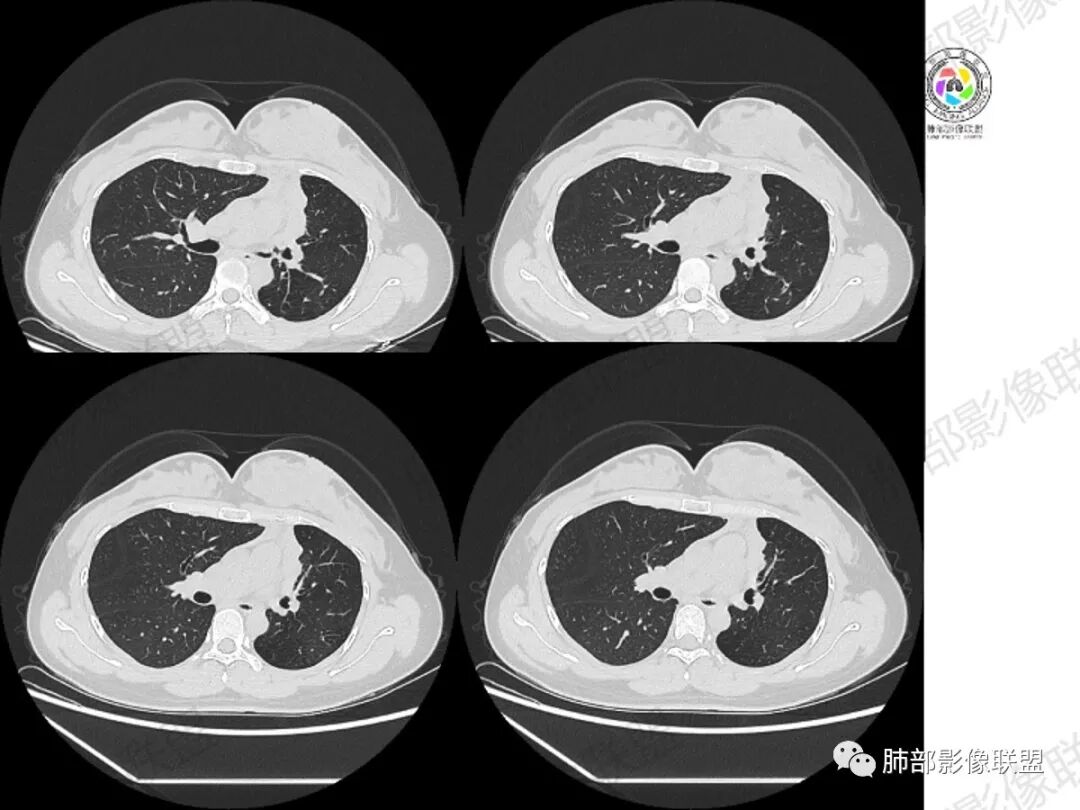

影像:左肺上叶支气管黏液栓伴实变不张,实变区域强化明显,小钙化灶,左肺下叶散在结节

年轻女性,慢性病程,左上叶纵隔旁大片实变,心脏纵隔左移,左主及左上叶支气管变窄呈针孔样,实变内可见斑点状钙化,显著不均匀强化,内可见低密度粘液拴,显著强化不支持TB,左上叶不张在腺癌少见,综合病变部位及强化表现考虑粘液表皮样癌,其次考虑类癌

女性,29岁,咳嗽咳痰,痰中带血1月余,CT示左肺尖胸膜下纵隔旁不规则实变影,内部可见小点状钙化灶,支气管略狭窄,增强可见低密度不强化区,粘液栓?实性成分明显不均匀强化,局部与左肺动脉分界不清,另左肺可见多发小结节,考虑为恶性,黏表可能,鉴别结核

年轻女性,咳嗦咳痰伴咳血1月多,ct可见纵隔左移,左肺容积减小,左肺上叶可见一不规则实变影,朝肺内侧边界清楚,部分边缘与纵隔界限模糊,临近支气管堵塞,内见点状钙化,增强不均匀强化,内可见多个低密度区,粘液?并与左肺动脉界限模糊,似受侵,考虑恶性,黏表?但病灶远端有多发小结节,卫星灶?结核待排

胸部CT:左肺体积缩小,左肺上叶前段纵隔旁胸膜下大片实变影,边缘清楚、匀齐、平直收缩,部分略膨隆,周围多发结节、树芽卫星灶,纵隔窗病灶与纵隔胸膜黏连,实变内多发点状钙化。平扫密度尚均匀,增强扫描不均匀明显强化,多个低密度区,呈仙人掌样,伴有条状血管影,考虑慢性炎症伴左上叶前段支气管闭塞,TB?鉴别黏表、腺癌等。